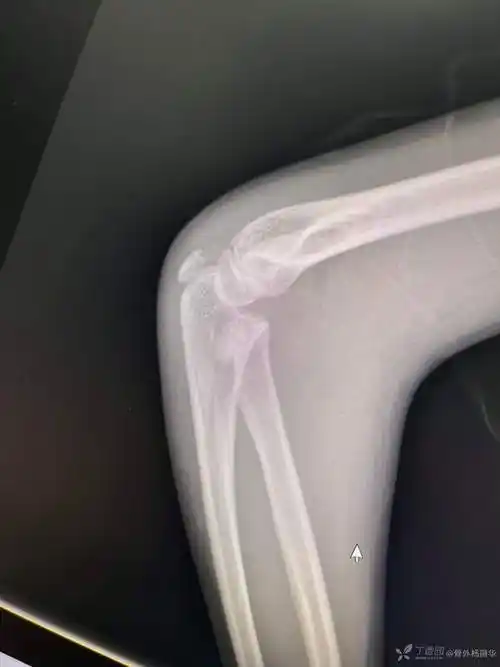

右侧桡骨头小头骨折经皮翘拨复位克氏针弹髓内固定